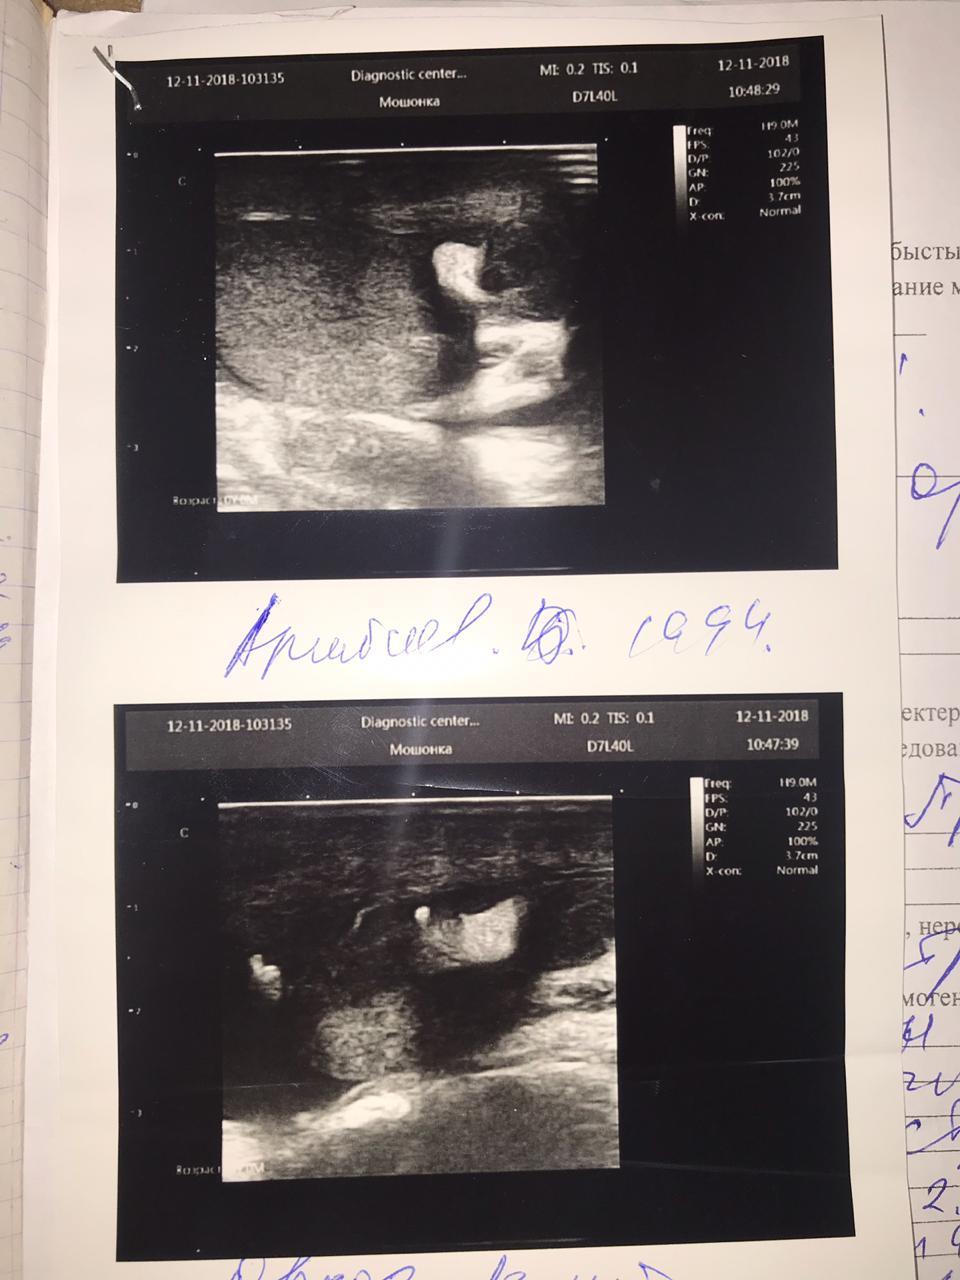

у меня ещё осталось восполнения яичка слева

Здравствуйте! Судя по результатам УЗИ - мочевой пузырь имеет циллиндрическую форму, имеется пиелоэктазия с обеих сторон, что свидетельствует о нарушении уродинамики . Надо сделать анализ крови на креатинин и сделать мультиспиральную компьютерную томографию почек, мочеточников, мочевого пузыря, простаты.(с контрастом). Присылайте результаты, проконсультируем. Удачи!